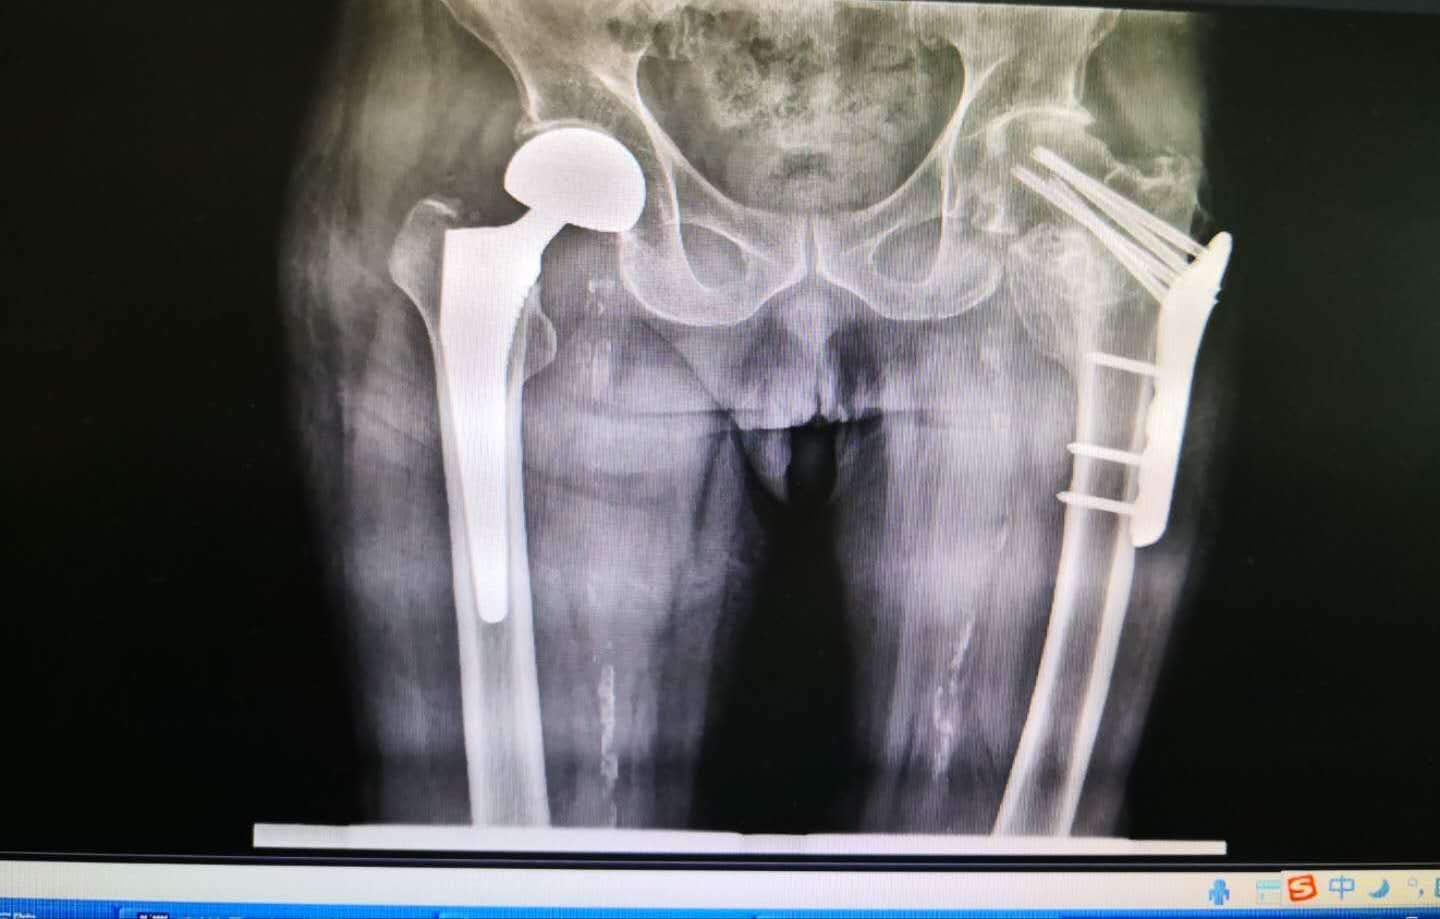

患者家属慕名来到沈阳医学院附属第二医院皇姑院骨外一科就诊。骨外一科陈铁主任带领陈玉楼副主任医师及团队成员在呼吸内科张永红医生会诊指导下,麻醉科魏之先主任及郑玉国医生麻醉配合下,于大年初三成功完成一例人工双动股骨头置换手术。手术成功后,患者转至重症医学科继续治疗。

(术后)